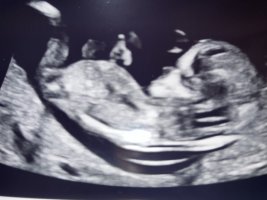

Ser ut som en jenteHåper det er nub på noen av disse (aner ikke hva man ser etter)

14+2 i dag, og navlestrengen lå mellom beina. Nurket sov og gjespet, ville ikke flytte på seg

Vis vedlegget 427759Vis vedlegget 427760Vis vedlegget 427761